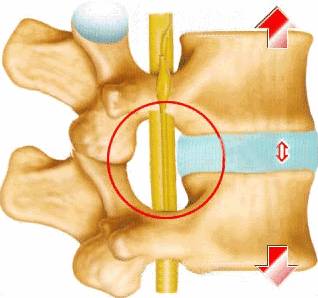

图片尺寸318x298中间类似于凝胶状的物质,称为髓核;以及与椎体相连的部分称为椎体终板

脊椎矫正原理